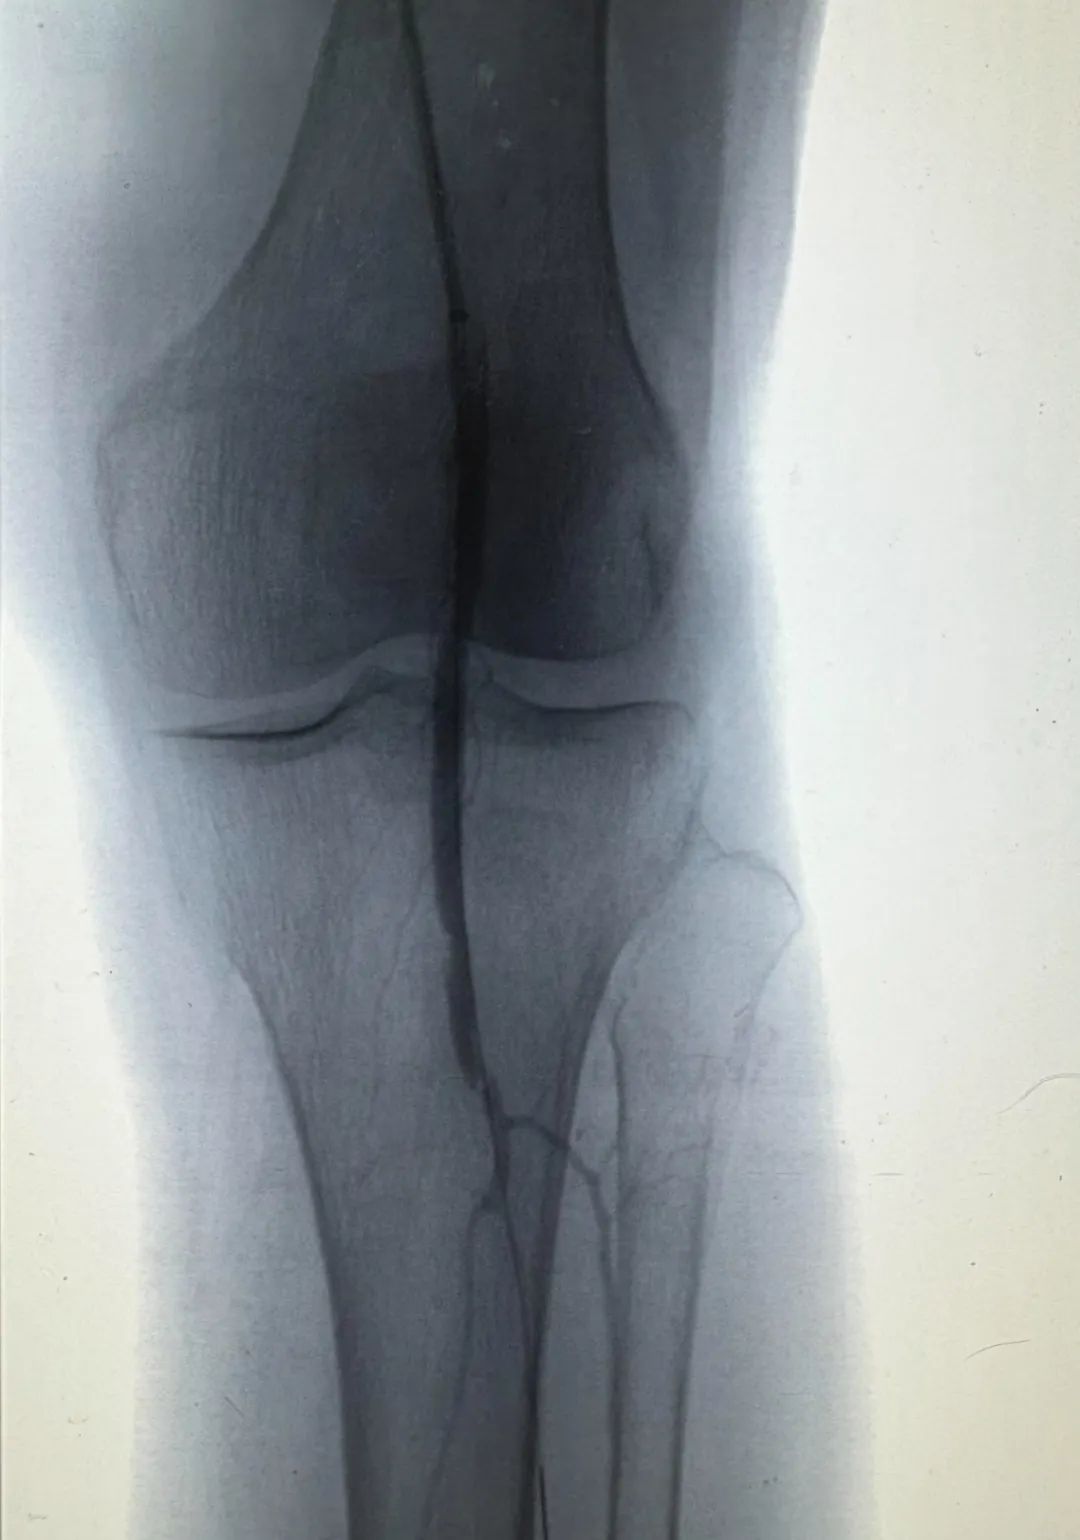

眼见着阿婆情况危急,奉城医院迅速开通绿色通道,血管外科团队在第一时间完成CT血管造影,显示老人左侧股动脉远端被长达20cm的血栓死死堵住,像一条腐烂的“血栓巨蟒”盘踞在血管里。然而,对于这样的超高龄患者来说,传统开刀取栓犹如“开膛破肚”,心衰、感染风险极高,但如今的奉城医院血管外科已拥有一把“秘密武器”——Roterax机械吸栓系统,正等待上演一场精密的“血管清道夫”行动。由血管外科主任宋菊民主刀,团队使用仅3mm粗的导管,如同操控微型手术刀:螺旋刀头高速旋转绞碎血栓,同步负压抽吸像“血管吸尘器”般将20cm长的血栓碎块全部吸出,45分钟精准“粉碎”,出血量还不到一纸杯。当造影显示股动脉远端血流通畅,即刻老人的脚就不疼了。手术室里响起欢呼声——没放一枚支架,却让93岁老人的血管“逆龄重生”。